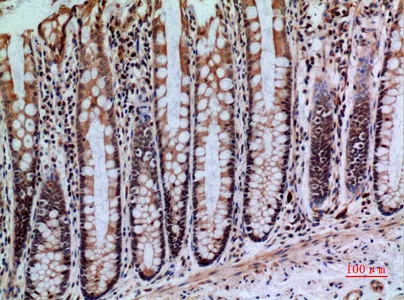

CD66e Rabbit Polyclonal Antibody

Cat: APRab08434

Size1:50μl Price1:$118

Size2:100μl Price2:$220

Size3:500μl Price3:$980

Size2:100μl Price2:$220

Size3:500μl Price3:$980